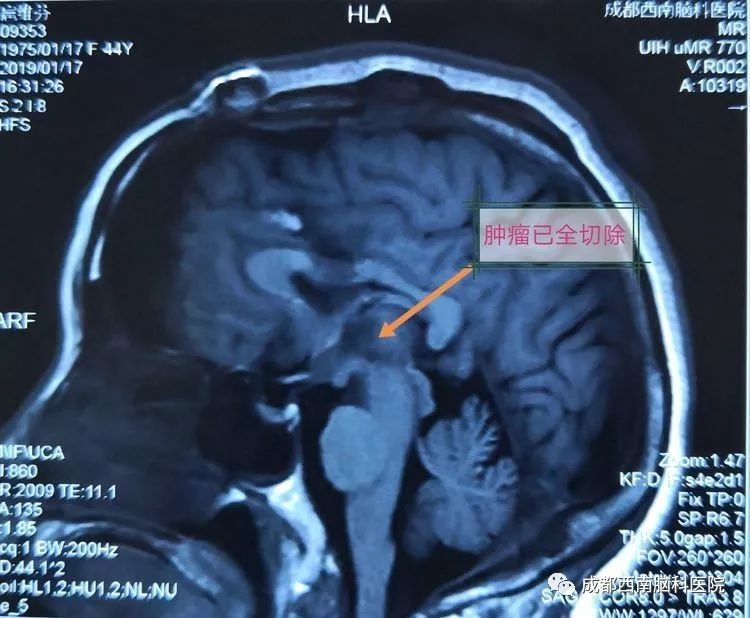

这样的情况下,她以“视物模糊伴重影18天,加重伴左眼睑下垂3天”入成都西南脑科医院。入院查体见左侧动眼神经麻痹,余未见异常。MRI检查显示,扈女士颅内的肿瘤位于中脑上端,经大脑向同侧丘脑发展,血管成像肿瘤显影良好,初步诊断为脑干肿瘤,海绵状血管瘤可能性大。

图片术前MRI矢状位影像

术后复查MRI显示已全部切除